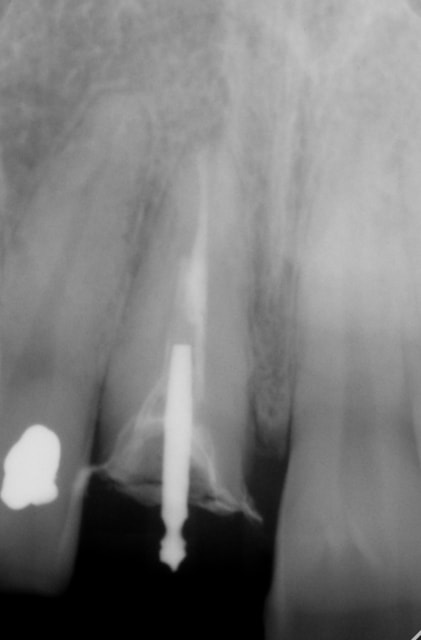

tenon large, cylindro-conique 2/3 à 3/4 de la racine

Et tant qu'à faire, je referais peut être aussi le traitement canalaire... (l'apex ne m'a pas l'air bien obturé)

La couronne dentaire est peut être longue, mais la racine l'est aussi, et a l'air plutôt robuste!

L'implant c'est aussi assez d'os mais aussi assez de "rose"